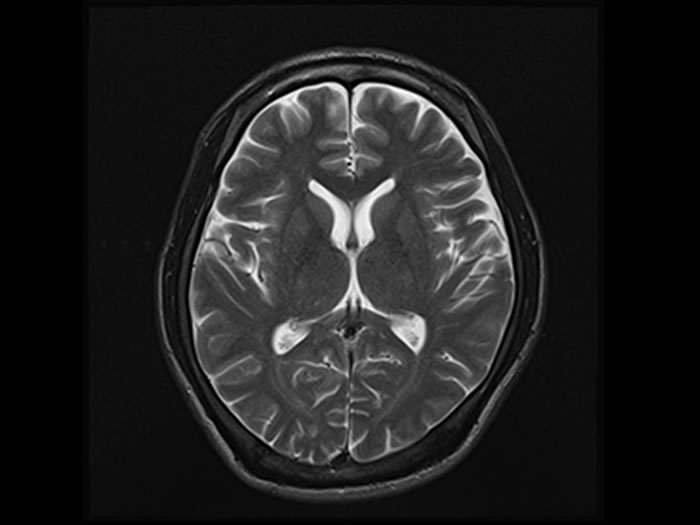

どんな検査をするの?

MRI検査・MRA検査

MRI検査は「脳全体」を視覚化して、

- 脳卒中(脳梗塞・脳出血・クモ膜下出血)の潜在

- 認知症の進行を示す「脳の萎縮」

などの早期診断が可能です。

どちらも放射線被曝のない安全な検査です。「頭が痛い」「めまいがする」などの症状があれば保険診療となります。まずは診察にお越しください。